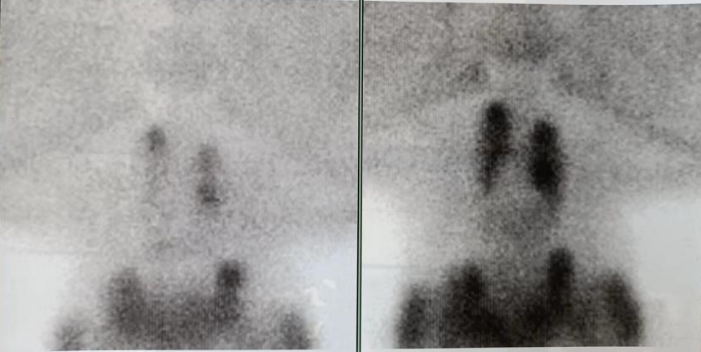

图5.术前甲状旁腺核素扫描

图6.术前甲状旁腺MIBI显像